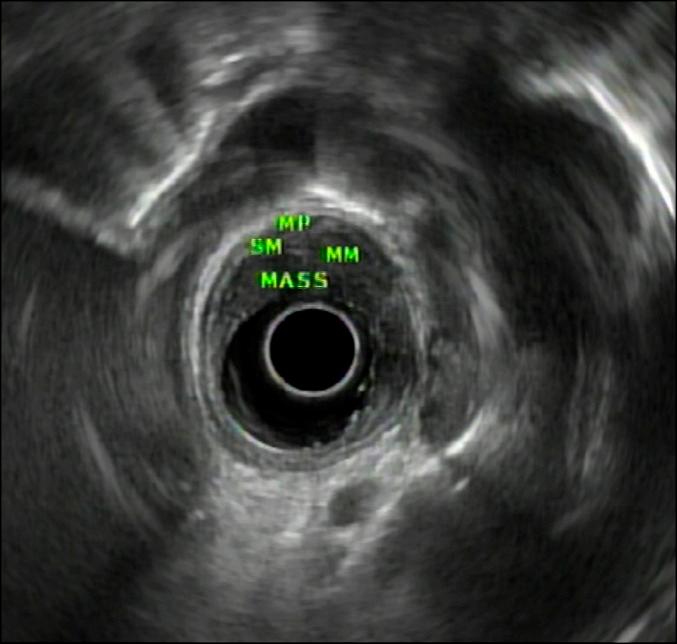

The typical appearance of Candida esophagitis is white plaque-like membranes within the esophagus. We describe a unique case of Candida esophagitis that presented as a bulky, malignant-appearing, positron emission tomography-computed tomography-avid mass on endoscopy. Esophageal candidiasis persisted despite a standard course of antifungal medications (fluconazole 400 mg daily for 14 days), and eradication was successful only after fluconazole 800 mg daily was administered. Malignancy was excluded based on 2 separate sessions of endoscopy with multiple biopsies and finally with endoscopic full-thickness resection assisted by preresection closure with an over-the-scope clip.

念珠菌性食管炎的典型表现是食管内出现白色斑块样膜状物。我们描述了一例独特的念珠菌性食管炎病例,在内镜检查中表现为一个体积较大、外观似恶性、正电子发射断层扫描-计算机断层扫描显示摄取增加的肿物。尽管接受了标准疗程的抗真菌药物治疗(氟康唑每日400毫克,共14天),食管念珠菌病仍持续存在,仅在每日给予800毫克氟康唑后才成功根除。基于两次独立的内镜检查及多次活检,最终通过内镜全层切除术(术前用套扎夹进行预切除闭合辅助)排除了恶性肿瘤。